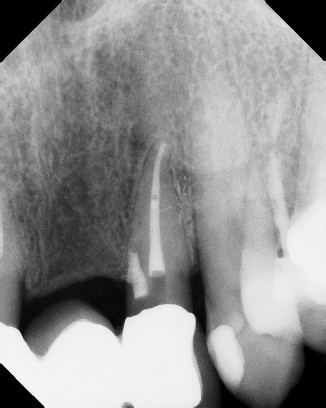

COMPLICATED ANATOMY LARGE LESIONS CALCIFIED CANALS PERFORATION / RESORPTION SEPARATED INSTRUMENTS SURGICAL CASES RETREATMENT / pOST REMOVAL OPEN APICES ACCESS THRU CROWNS Root Canal Case Portfolio